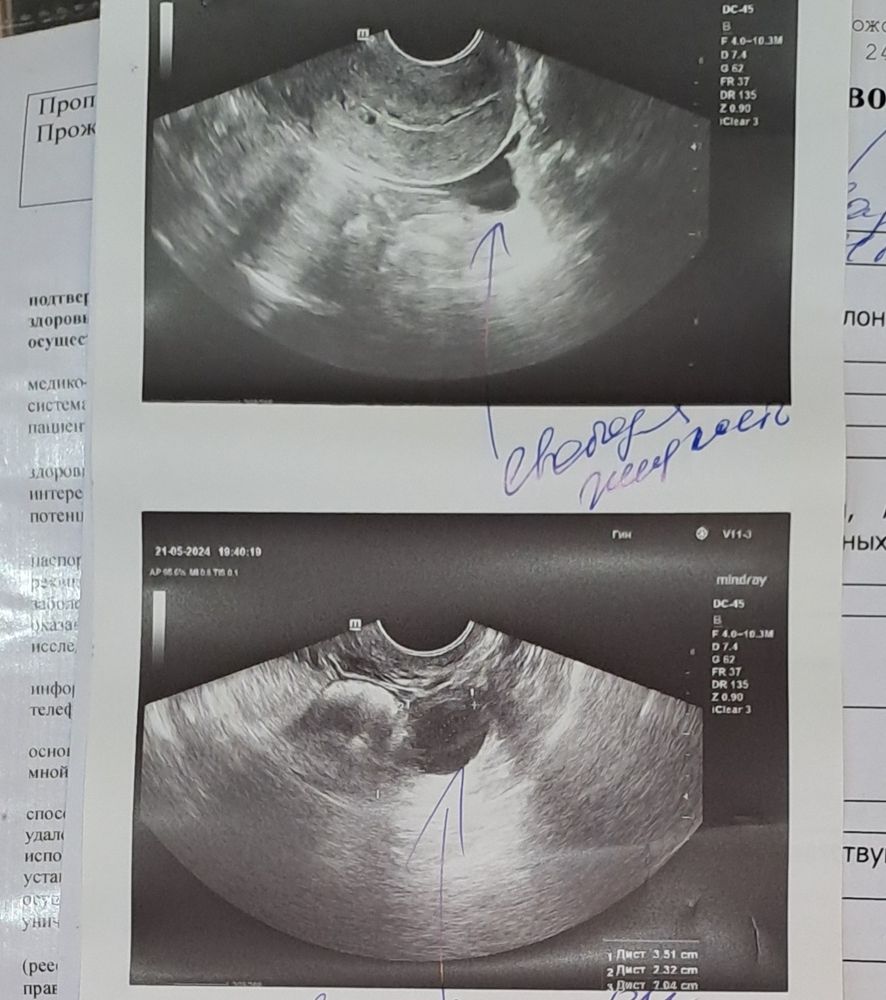

ЖТ или ДФ ???

Изображение

Девочки! Понимаю заезженный вопрос, но может кто на опыте по фото определит не опираясь на ДЦ, цикл не стабилен. Желтое тело или фолликул? Узист написала ЖТ и т